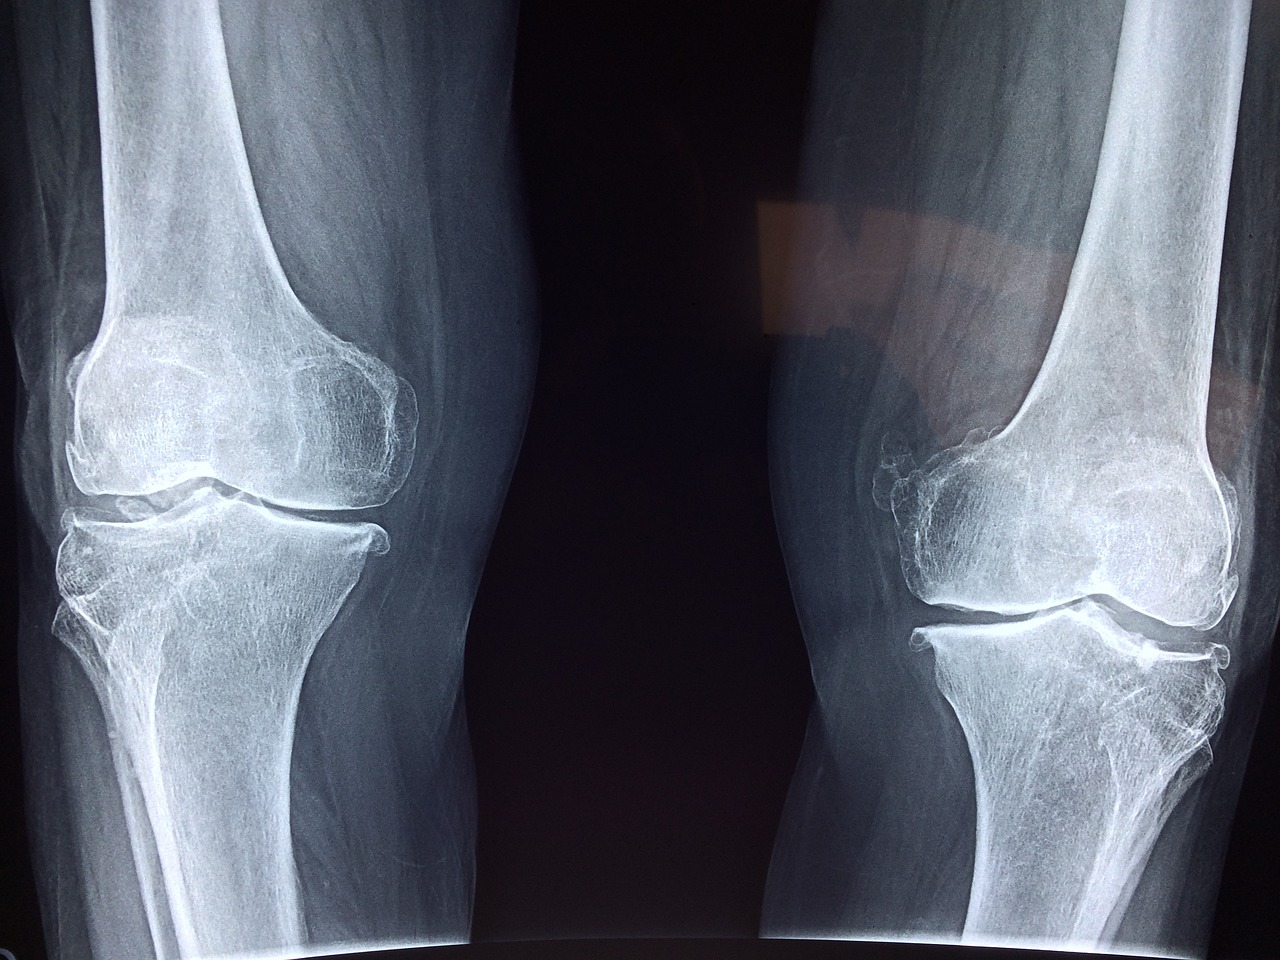

2. 골다공증 증상

골다공증 초기에는 크게 인지하지 못합니다. 특별한 증상이 없기 때문입니다. 초기에는 척추뼈가 약해지고 척추변형이나 키가 줄어드는 증상이 발견됩니다. 심해지면 척추가 체중을 이겨내지 못하여 척추가 앞쪽으로 휘어지게 됩니다.

이는 곧 골절로 이러지게 되는 위험을 높이게 됩니다. 심하면 허리를 구부리거나 기침등 간단한 생활에서도 뼈가 쉽게 부러지기도 합니다. 50~70세 여성의 경우 손목골절부터 발생하는 경우가 많습니다. 70세 이후에는 고관절이나 척추골절이 흔하게 발생됩니다.

이렇게 골다공증은 초기에는 증상이 없지만 골절이 생기게되면 통증을 느끼게 되고 골절부위에 다양한 증상이 동반됩니다. 모든 부위에 골절이 일어날 수 있고 손목뼈, 척추, 고관절 골절이 가장 흔하게 나타납니다.